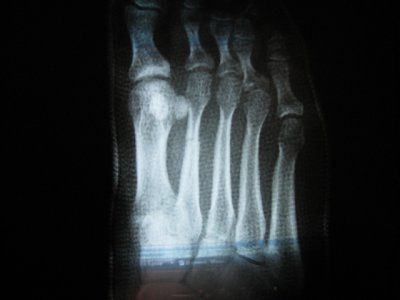

Здравствуйте!Помогите, пожалуйста. Стопу переехала машина. Сломаны 2 плюсневые кости (без смещения). В больнице положили круговую повязку (пластик) на 6 недель. Когда сняли, сделали контрольный снимок, сказали, что срастается. Но на снимке видна трещина. Можно ли считать такое срастание нормальным? Заранее спасибо.

снимки после снятия гипса: